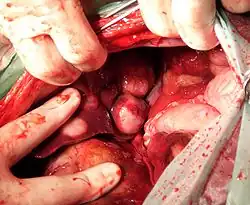

Bei Krebserkrankungen werden neben dem Primärtumor in der Regel die Lymphknoten der Abflussbahn und „suspekte“ Lymphknoten aus der vorhergehenden Diagnostik (körperliche Untersuchung, Computertomografie, Magnetresonanztomografie) mit entnommen und histopathologisch auf regionäre Metastasen untersucht. Bei unklarer Lymphabflussbahn, z. B. bei Hauttumoren, wird über das Einspritzen radioaktiv markierter Farbe der Sentinel-Knoten („Wächterknoten“) mittels Geigerzähler und Farbmarkierung operativ aufgesucht. Lymphknotenmetastasen verschlechtern die Prognose und führen bei kurativem Ansatz zu einer aggressiveren Therapie.